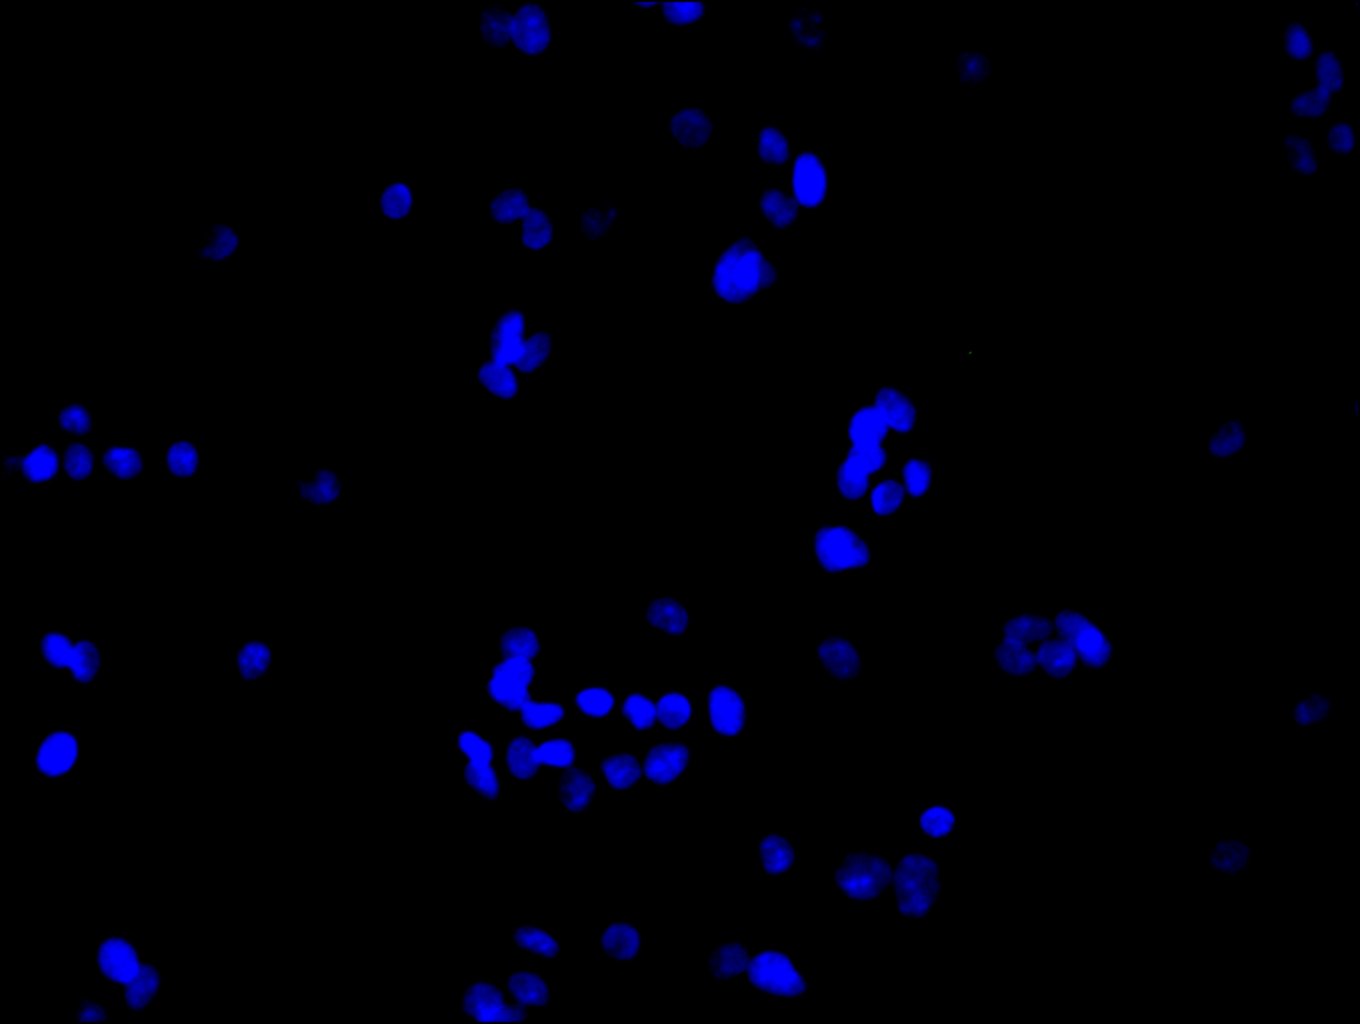

Immunofluorescence staining of HepG2 cell with CSB-PA887023ESR1HU at 1:30, counter-stained with DAPI. The cells were fixed in 4% formaldehyde and blocked in 10% normal Goat Serum. The cells were then incubated with the antibody overnight at 4C. The secondary antibody was Alexa Fluor 488-congugated AffiniPure Goat Anti-Rabbit IgG(H+L).

Immunofluorescence staining of HepG2 cell with 5% goat serum, counter-stained with DAPI. The cells were fixed in 4% formaldehyde and blocked in 10% normal Goat Serum. The cells were then incubated with the antibody overnight at 4C. The secondary antibody was Alexa Fluor 488-congugated AffiniPure Goat Anti-Rabbit IgG(H+L).